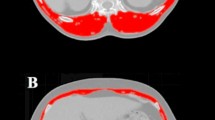

We used the skeletal muscle index (SMI), a key marker to assess sarcopenia, for identification of sarcopenic patients. The SMI was assessed using the preoperative computed tomographic re-staging scans by measuring the cross-sectional muscle area at the third lumbar vertebral level. According to Prado et al., who validated SMI cut-off values in a Western population, following cut-off SMI values were used to define sarcopenia: 52.4 cm2/m2 for males and 38.5 cm2/m2 for females14. Based on these cut-off values, the study population was divided into a sarcopenic and a non-sarcopenic group.

Mean BMI was 26.6 kg/m2 and mean SMI was 43.1 cm2/m2. Pearson’s correlative analyses demonstrated a correlation between BMI and SMI (r = 0.606; p < 0.0001). Based on SMI cut-off values as described above, 168 patients (82%) were classified as having sarcopenia.